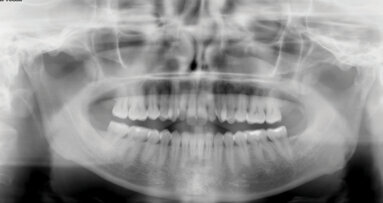

Dále byl vyhodnocen kefalometrický snímek (obr. 9), ortopantomogram (obr. 10) a provedena analýza modelů (obr. 11–15).

Po vyhodnocení dat, jsme se dohodly s pacientkou, že pro zlepšení profilu a postavení zubů bude nutná extrakce 4 premolárů.